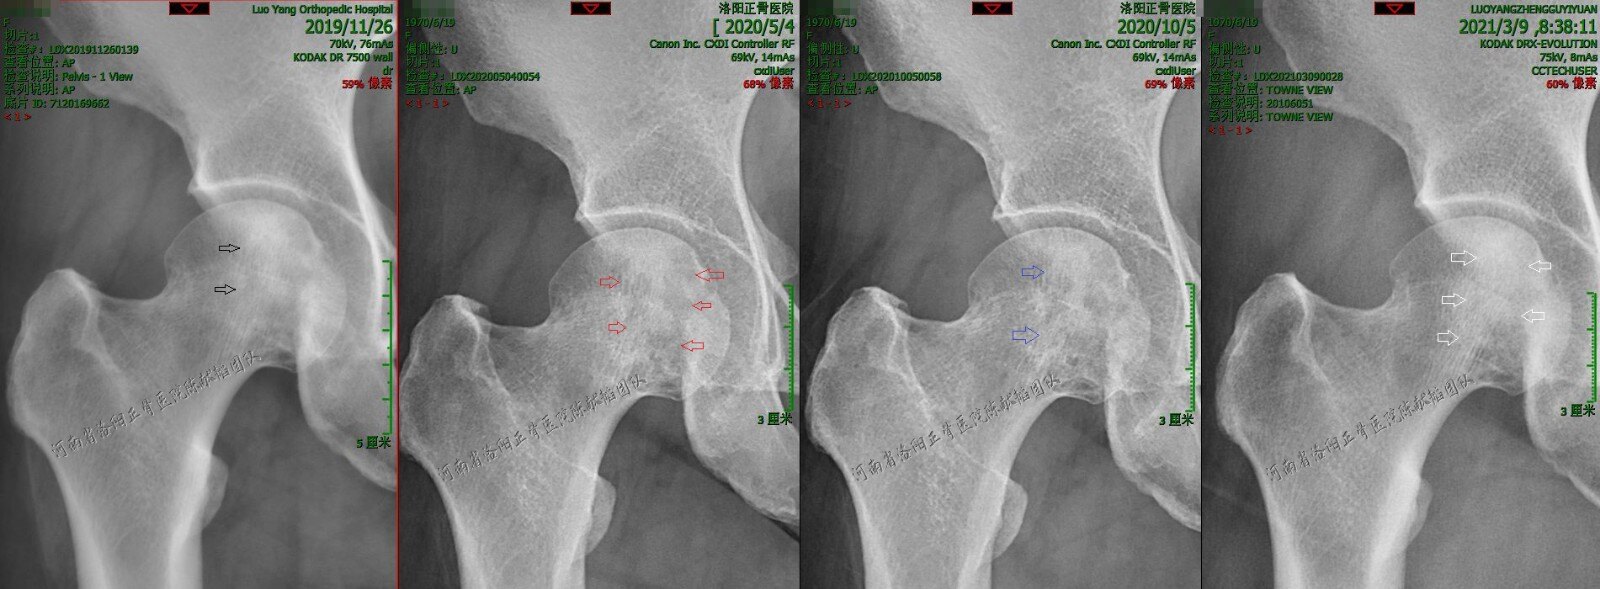

"颠倒黑白"真的吓死人,再谈股骨头坏死的影像特点